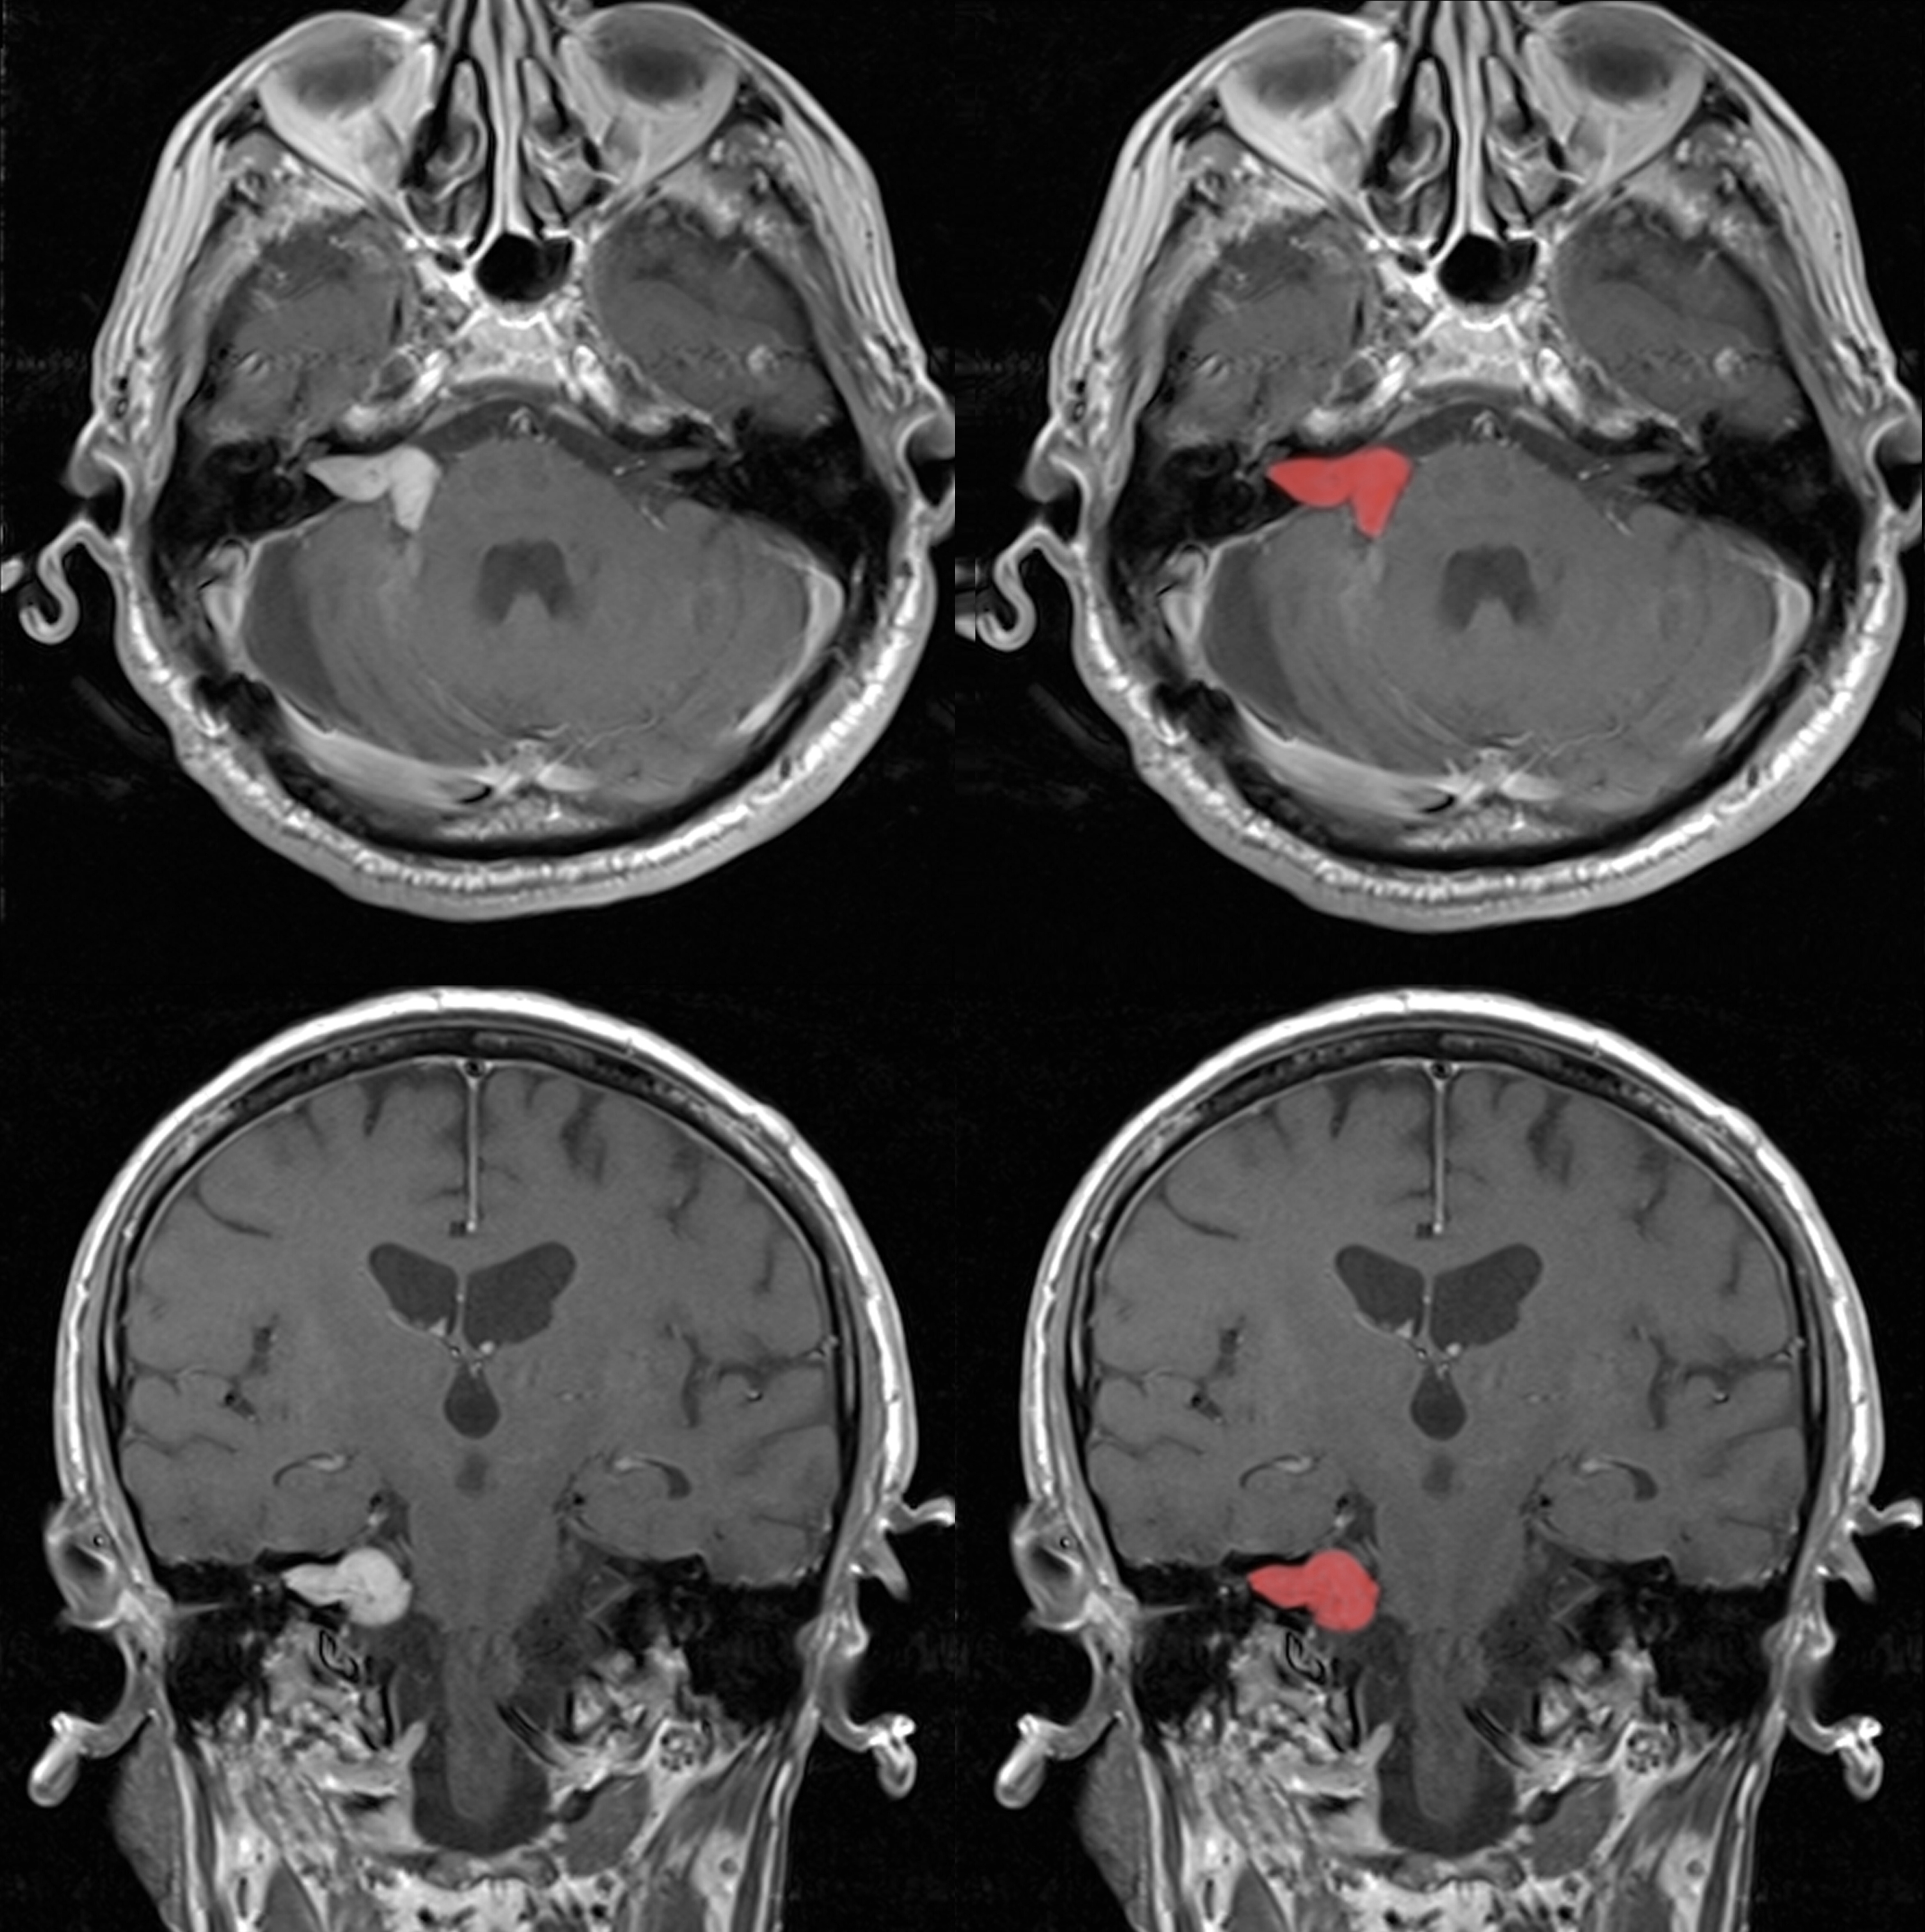

CT/MRI 데이터를 바탕으로 실제 수술 환경과 유사한 의료 술기 훈련 환경을 구축합니다.

04 의료용 3D 모델링 Medical 3D Modeling & Visualization

가상 시뮬레이션 및 학술 연구용 콘텐츠 개발에 최적화된 고정밀 해부학 3D 모델링 솔루션을 제공합니다.

고정밀 해부학 구조 구현 High-Fidelity Anatomical Modeling

의료 데이터를 직접 해석(Segmentation)하여, 자동화 도구가 놓치기 쉬운 미세한 인체 구조까지 정교하게 추출합니다.